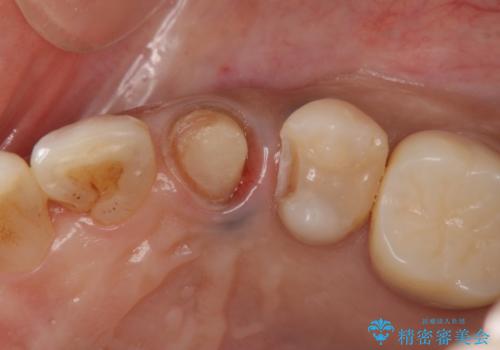

治療途中

左:虫歯を除去したところ。遠心が歯ぐきより深い状態です。中:そのままかぶせようとすると、遠心が歯ぐきが腫れやすい状態です。右:エクストリュージョンをしたことで、遠心の歯ぐきの腫れが収まっていることがわかります。

目立たないマウスピースで2ヶ月くらいで十分引っ張り出すことができました。

その後、手術をしてしっかり骨の位置を修正し、歯を引っ張り出した時に増殖した余分な歯ぐきを薄くする歯周外科治療も行なっています。